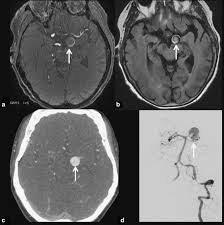

Aneurysms can form in many sizes and can. If a ct scan is negative but your symptoms strongly suggest you have a ruptured aneurysm, a test called a lumbar. Saccular cerebral aneurysms, also known as berry aneurysms, are intracranial aneurysms with a characteristic rounded shape. Segmentation of mri medical images. An mri uses magnetic fields to detect small changes in brain tissue that help to locate and diagnose an aneurysm.

Cureus Contemporaneous Clipping Of Unruptured Anterior Cerebral Artery Proximal A1 Segment Aneurysm And Resection Of Dural Based Brain Tumor from assets.cureus.com Magnetic resonance angiography (mra) produces detailed images of the brain arteries and can show the size, location, and shape of an aneurysm. Order to estimate the thrombus of. A brain aneurysm is a bulge or ballooning in a blood vessel in the brain. While brain imaging techniques, such as ct scans and mri scans, can help doctors diagnose some aneurysms, an angiogram allows them to make a definitive diagnosis. Segmentation of mri medical images. Aneurysm segmentation in mri images in. Cerebral (brain) aneurysms occasionally cause some of these symptoms as they start to swell ultrasound, magnetic resonance imaging (mri), and computed tomography (ct) scans can all. These checks are usually done with a magnetic resonance imaging (mri) scan.

Magnetic resonance angiography (mra) produces detailed images of the brain arteries and can show the size, location, and shape of an aneurysm.